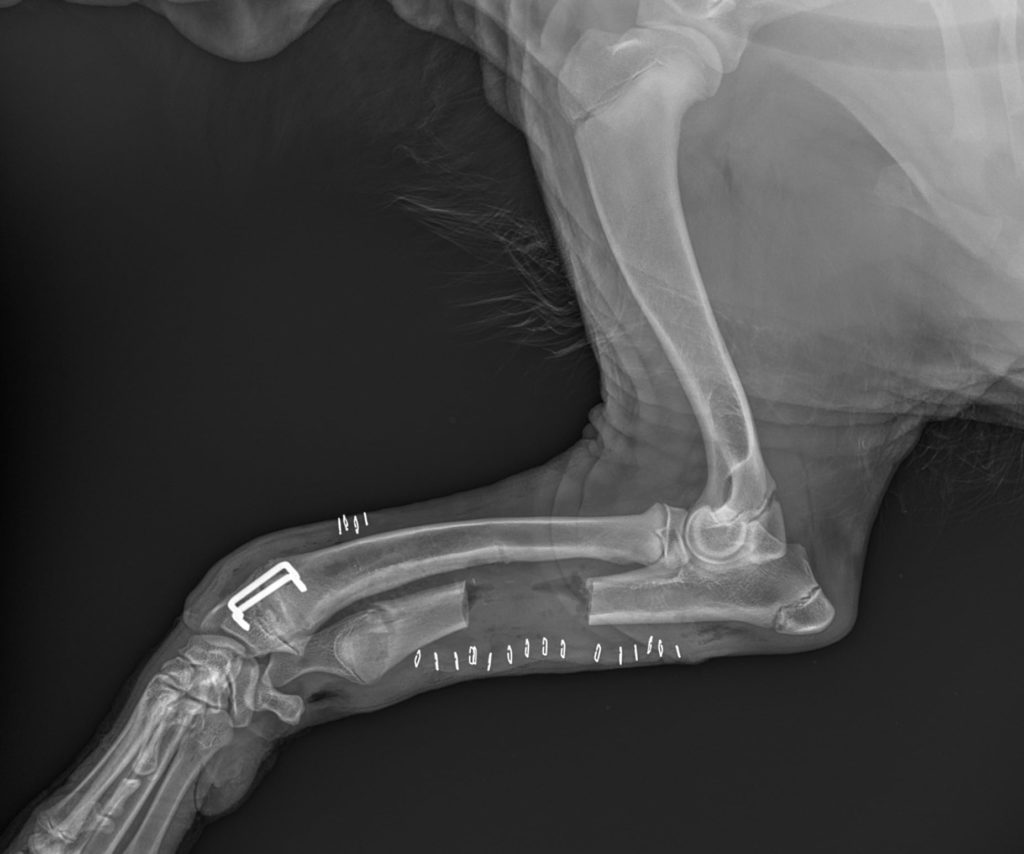

Poniżej prezentujemy zastosowanie klamer kostnych w leczeniu zespołu krzywej kości promieniowej u psa.

Zdjęcia przedstawiają osteotomię kości łokciowej i częściową epifizjodezę kości promieniowej.